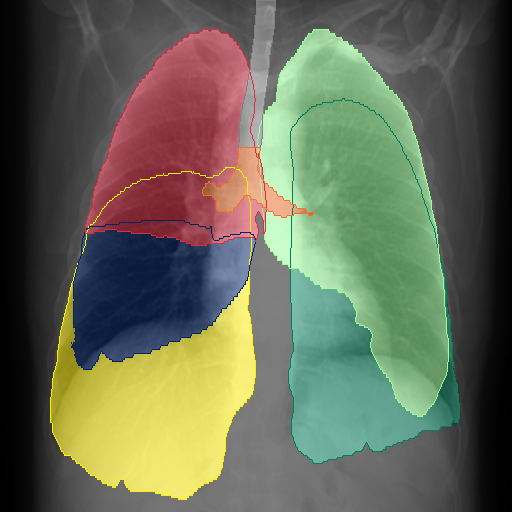

We show qualitative results for frontal projections in Fig. 2. We show a subset of classes belonging to the supercategories lungs, vascular systems, bones, and abdomen/digestive system. The predictions show minor deviations at the boundaries of the individual classes of the respiratory and vasculature system, while some inaccuracies become visible in the abdominal area. The qualitative results for the lateral projections are displayed in Fig. 2. Akin to the frontal view, the predictions show smoother borders but align with the ground truth. Apart from this, the segmentations provide matching insights on the thoracic anatomy with a slight deviation from the ground truth for both frontal and lateral views.

We display qualitative results in Fig. 3. The annotators tend to be content with most annotations. There are edits at the extensions of the esophagus, trachea, and aorta and corrections of the lower ribs. There is little consensus for classes in the abdominal area, such as the stomach, as seen on the right of Fig. 3 . In contrast, the annotators often align for bone classes.